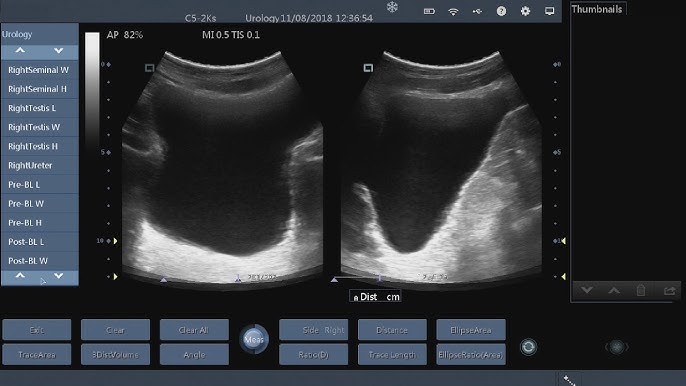

To assess the precision of five different calculation methods in real-time bladder volume measurement. Web volume length width thickness π6. Web The amount of urine a childs bladder should hold can be calculated by the following equation.

Web In your sagittal plane view you measure the length of the bladder. Web Bladder Volume Calculation Formula. Web Bladder ultrasounds can be used independently for volume measurements or in conjunction with other exams such as FAST renal studies and pelvic ultrasounds.

The protocol includes an edge-detection algorithm. 2 x age years 2. Web Estimates bladder volume based on ultrasound shape length width and height measurements.

Multiplying these numbers x 07 will give you your bladder volume. While this formula has been widely used in the literature it has limitations.